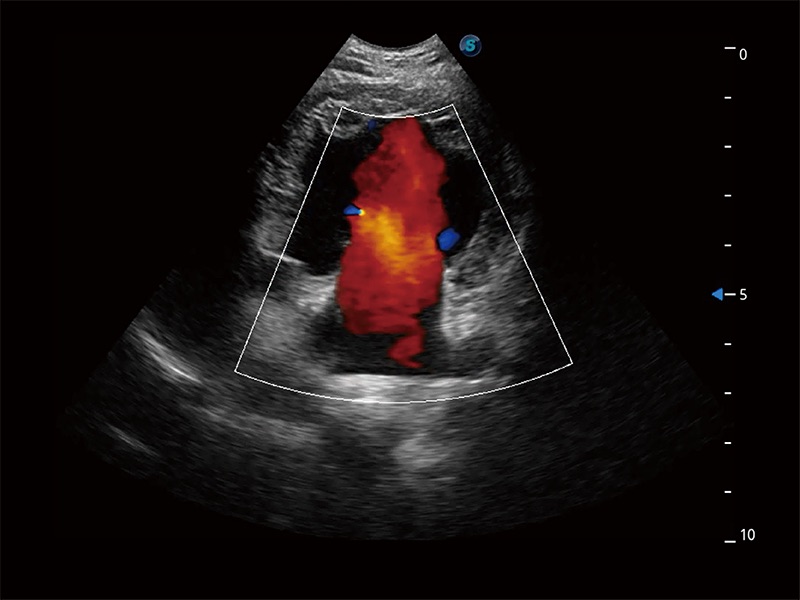

ProPet 80 配备了丰富的心脏探头群、先进的成像技术和专业的心脏测量工具,可帮助动物医生为不同体型和生理结构的动物提供心脏和心肌功能的全面评估。

能够增加心肌组织与血流之间的区别。对于心脏扫查困难的动物,可提供更好的心内膜边界的显示。